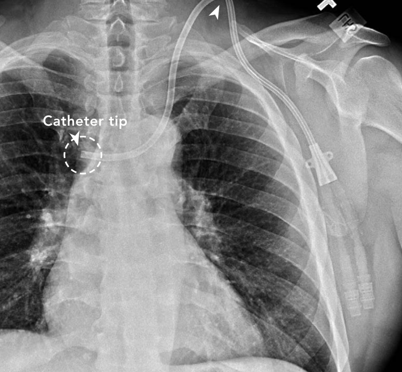

![]() Malpositioned dialysis catheter. Vachharajani, Atlas of Dialysis Vascular Access, 2010. | Difficulty aspirating from the catheter High arterial or venous pressures on dialysis Poor blood flows | Obtain a chest x-ray to check the location of the catheter Consult interventional radiology or nephrology for guidewire catheter exchange |

![]() Catheter-related atrial thrombus. Yang et al., JVS, 2018. | Frequently asymptomatic, incidental finding on imaging (95-99% of cases) | Systemic anticoagulation with warfarin or novel anticoagulant as for treatment of DVT Catheter removal or exchange (Figure 2) |

Table 1. Non-infectious hemodialysis contraindications and their suggested management.